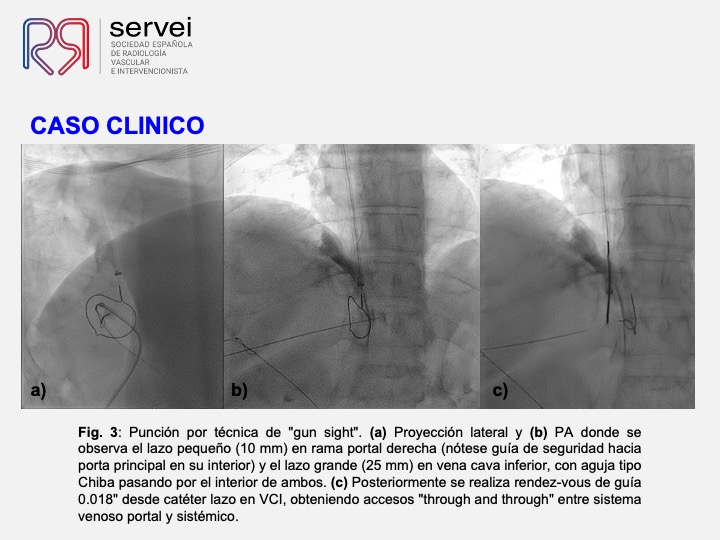

DIPS con técnica de “gun-sight”. Paciente con Síndrome de Budd-Chiari y eventual trombosis protésica